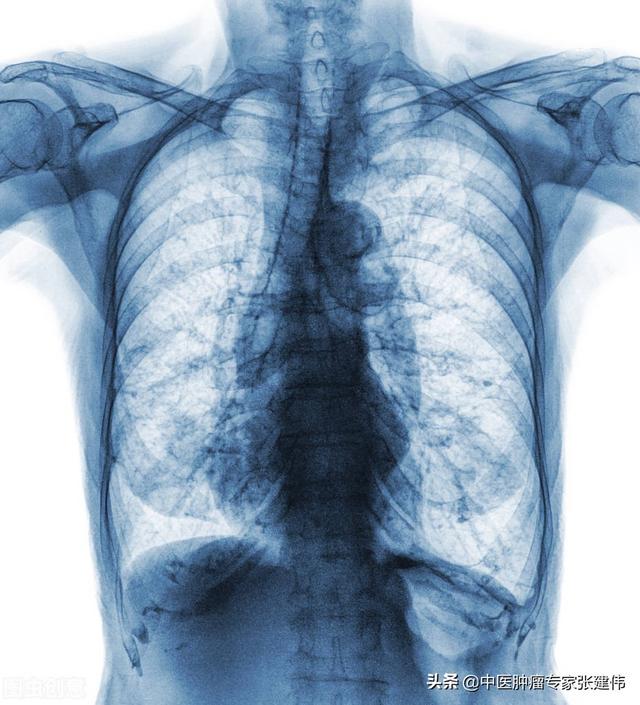

Le moyen le plus efficace de vérifier la présence de foyers fibrotiques ou calcifiés dans les poumons consiste à effectuer une radiographie ou un scanner thoracique, mais la clarté et la précision du scanner thoracique sont évidemment plus élevées que celles de la radiographie, et son prix est un peu plus élevé.

Les foyers fibreux et les foyers calcifiés se manifestent à l'imagerie thoracique.